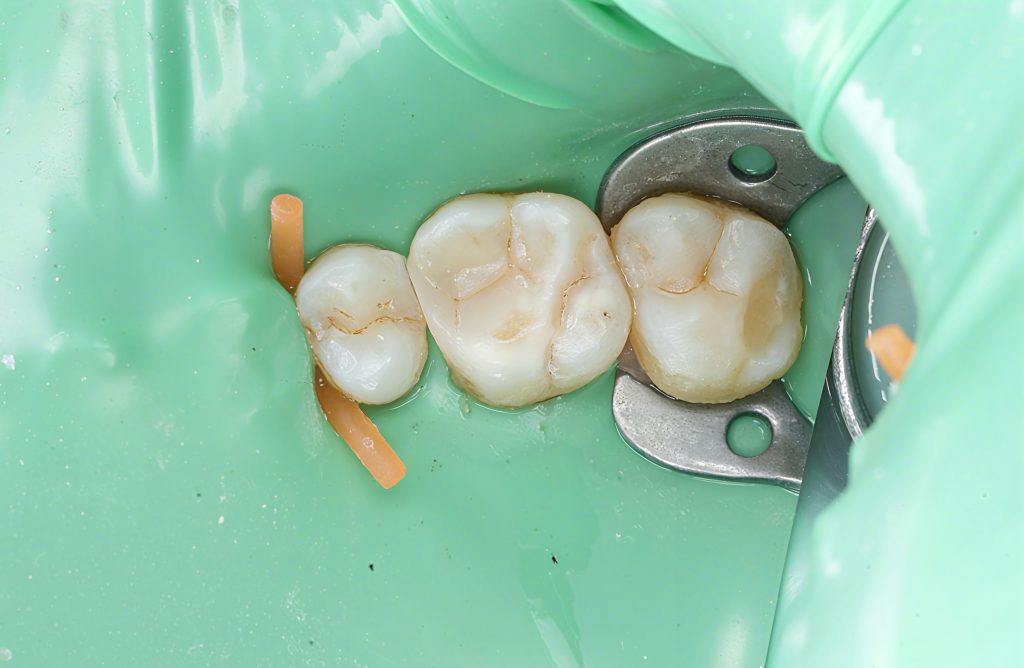

A lower posterior tooth presented with an incipient proximal lesion visible clinically and radiographically. The goal was simple: treat early disease with minimal preparation, preserve enamel, and rebuild a tight contact with a controlled adhesive workflow.

The tooth was isolated with a heavy-weight rubber dam. Caries was removed selectively until a clean enamel–dentin interface was reached. No extension for convenience. No unnecessary sacrifice of structure.

2. Isolation & Access

Rubber dam placement ensured a clean field.

Only undermined enamel and infected dentin were removed—nothing more.

3. Matrix, Wedge & Separation

A tight sectional matrix with a soft wedge gave:

- A clean emergence profile

- Predictable contact strength

- Gingival seal control